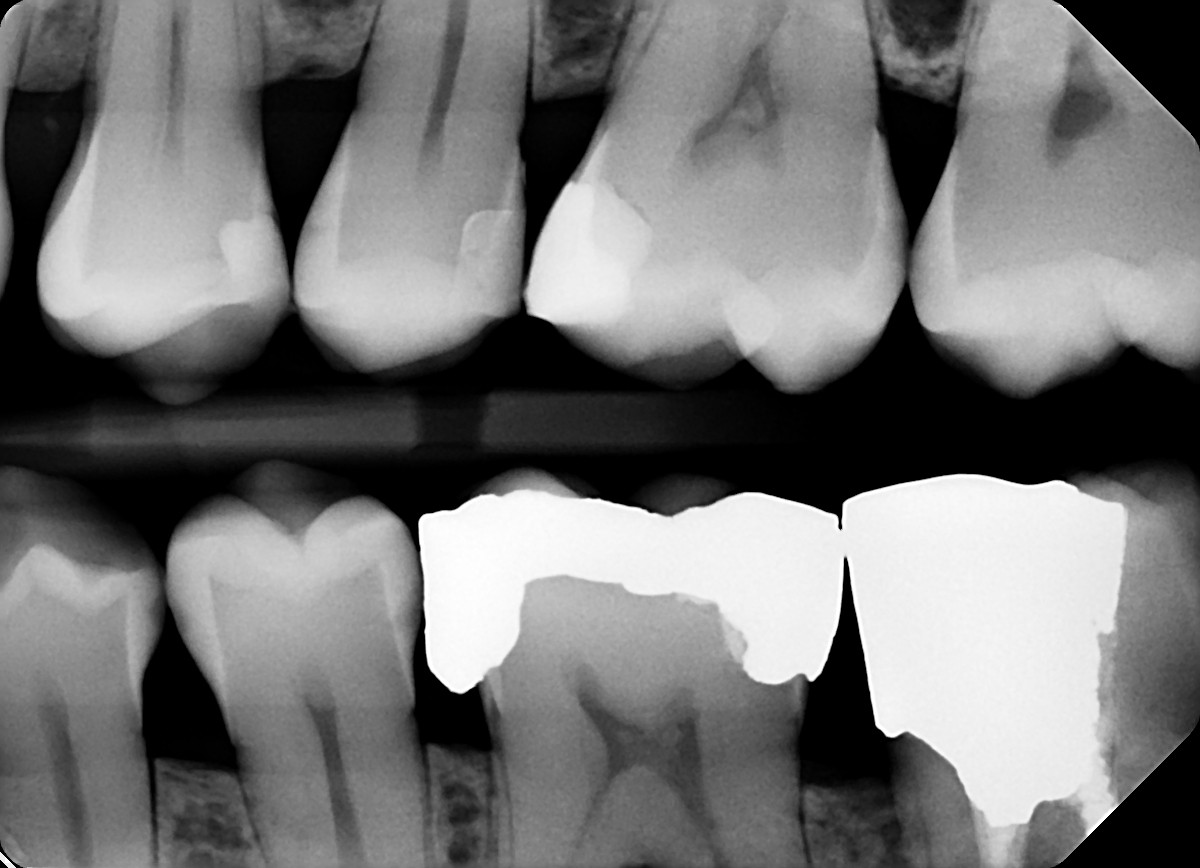

6. On which surface a recurrent caries can be detected?

7. On which surface a recurrent caries can be detected?

No cavity can be detected, restorations on 1.7, 4.6 and 4.7 are porcelain onlays